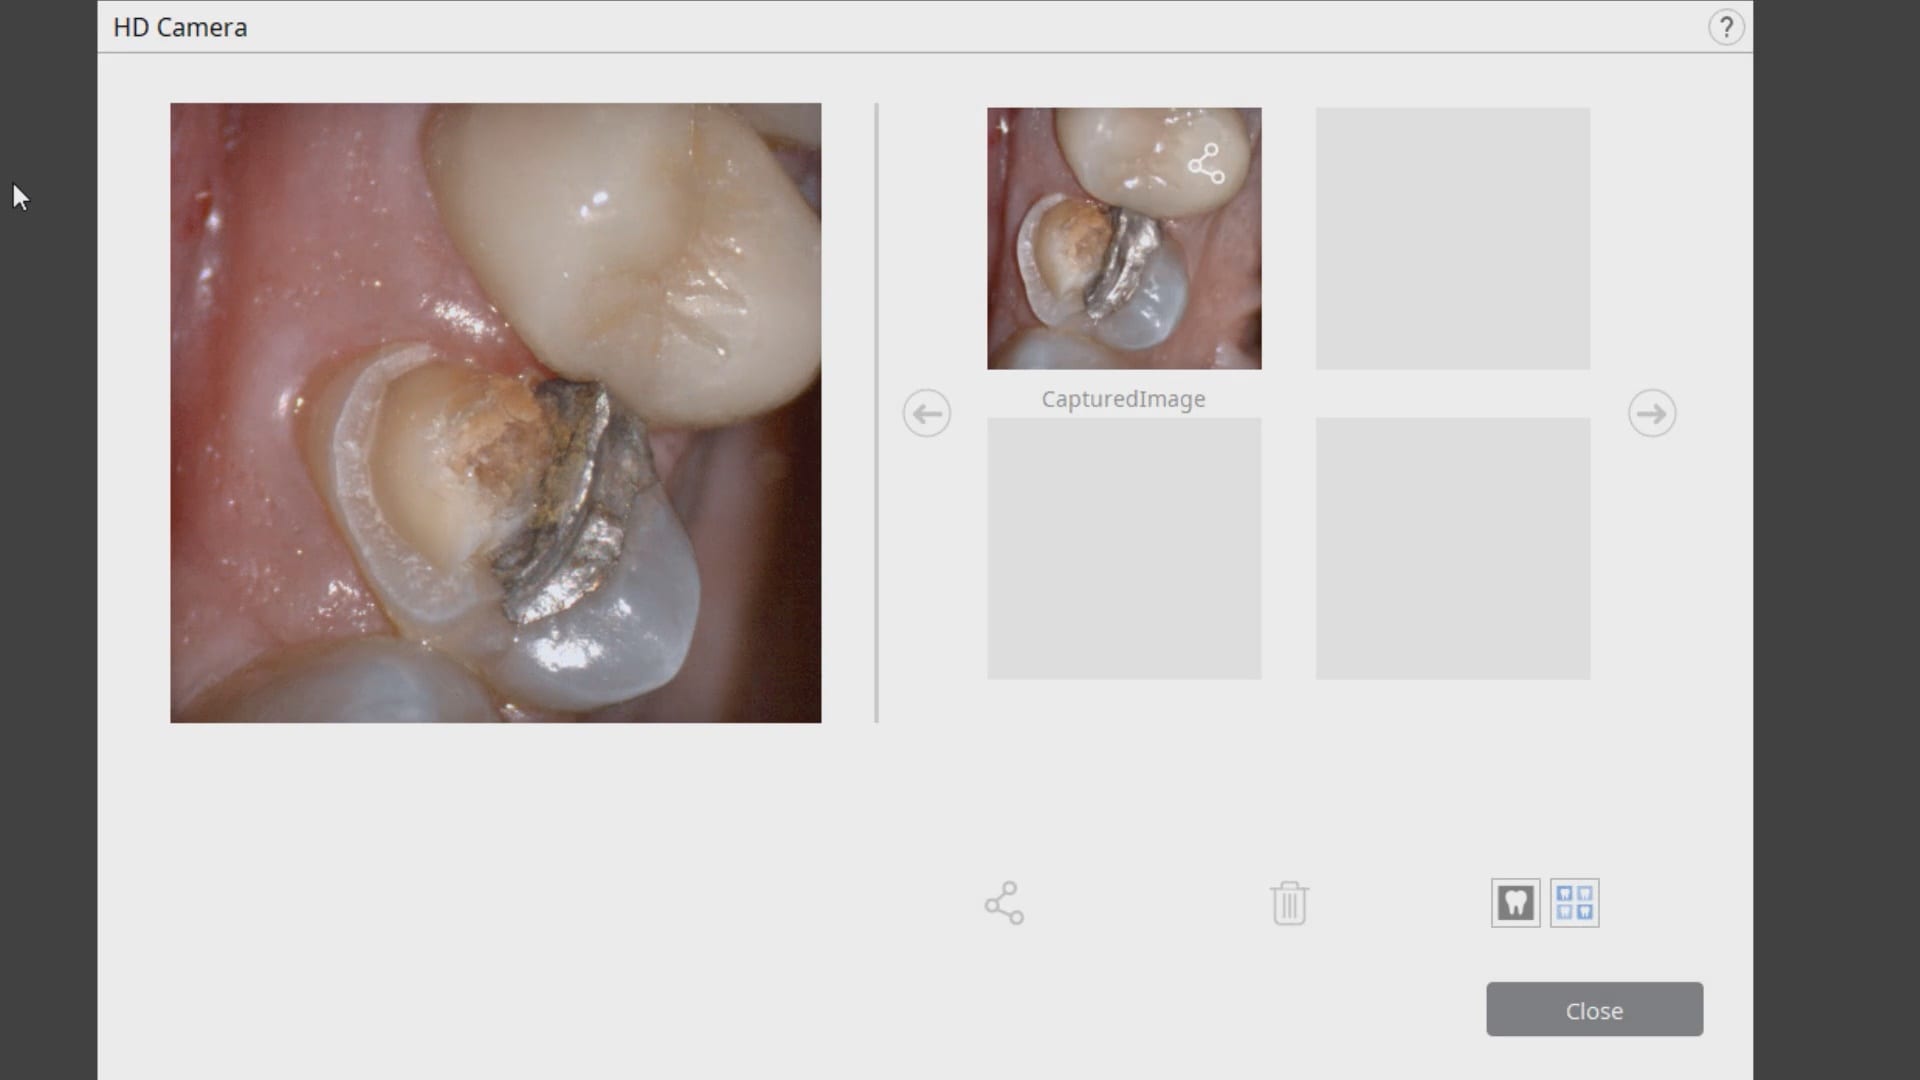

November 19, 2019Have you ever compared the milled product with the designed restoration? We scanned with the medit i500, designed with exocad and milled with coritec. after try-in, we scanned the restoration […]